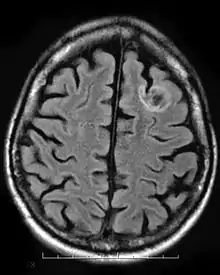

Oligodendroglial tumors manifest in glial cells, which are responsible for supporting and protecting nerve cells in the brain. The tumor develops over oligodendrocytes and is usually found in the cerebrum around the frontal or temporal lobes. The tumors can either grow slowly in a well-differentiated manner delaying the onset of symptoms, or they can grow rapidly to form an anaplastic oligodendroglioma. The symptoms for this type of tumor include headaches and visual problems. Additionally, blockage of ventricles could cause buildup of cerebral spinal fluid resulting in swelling around the tumor. The location of the tumor may also affect the symptoms since frontal lobe tumors can cause gradual mood or personality changes while temporal lobe tumors result in coordination and speech problems.[11]